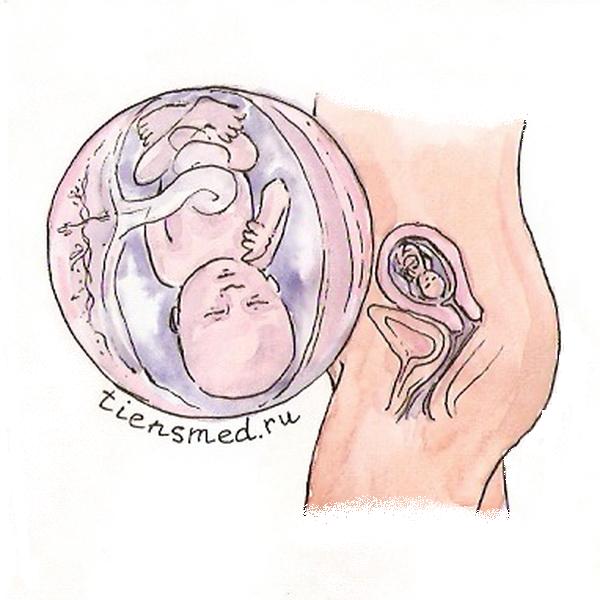

Расположение плода на 15-й неделе беременности: фотографии и иллюстрации